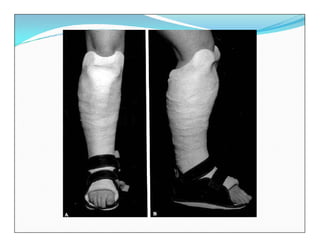

Tratamiento

 Ortopédico:

 reducción cerrada y yeso muslopedico

 Yeso Funcional (Sarmiento)

 El manejo cerrado u Ortopédico se lleva a cabo en

aquellos pacientes con fracturas generalmente

cerradas que tengan un trazo estable que permita

mantener una posición “aceptable” entre los

fragmentos luego de realizar la reducción y que

conserve esta reducción con una férula o con un yeso

circular.

Fracturas Diafisiarias deTibia  El manejo cerrado u Ortopédico se lleva a cabo en aquellos pacientes con fracturas generalmente cerradas que tengan un trazo estable que permita mantener una posición “aceptable” entre los fragmentos luego de realizar la reducción y que conserve esta reducción con una férula o con un yeso circular.